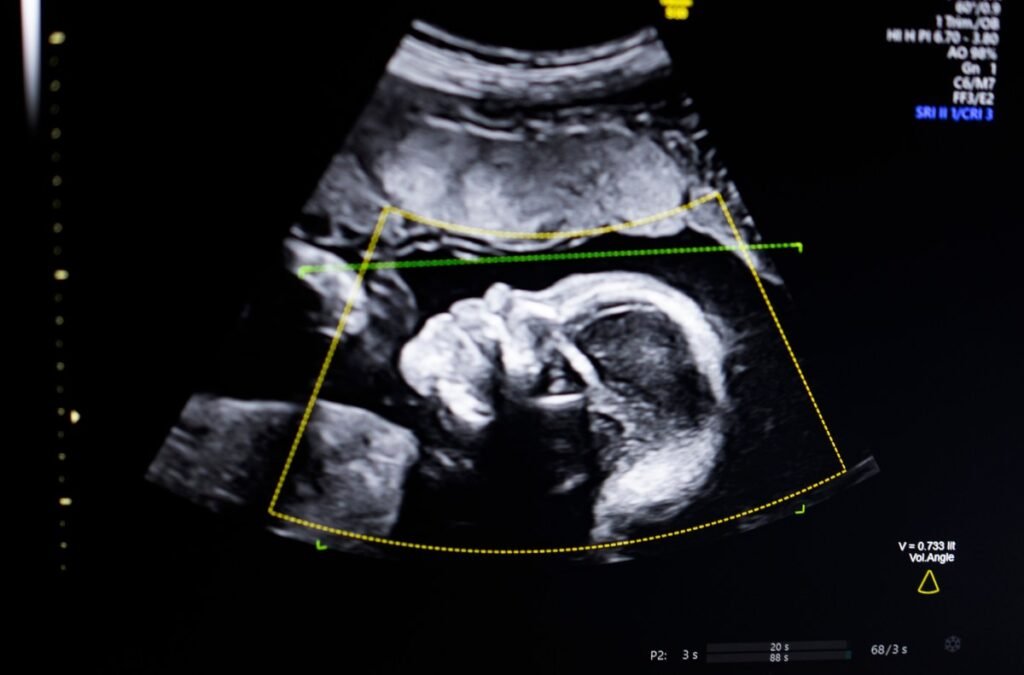

Bustami believes that the prenatal ultrasound has become a cornerstone of pregnancy monitoring, but when ultrasound images are of poor quality, it can lead to misdiagnosis. So, he and his team trained their AI models on over 11,000 ultrasounds to tackle this issue. But the real challenge was ensuring that their tech could perform under real-world conditions, especially for populations at high risk.

After studying computer science at UC Irvine and learning to code, Bustami teamed up with a talented crew – Salam Khan, Chaskin Saroff, and Dr. Hisham Elgammal – to bring his vision to life in 2021. Their AI-powered software uses computer vision to review fetal ultrasound quality, detect anatomical completeness, automate reporting, and integrate seamlessly into medical workflows.